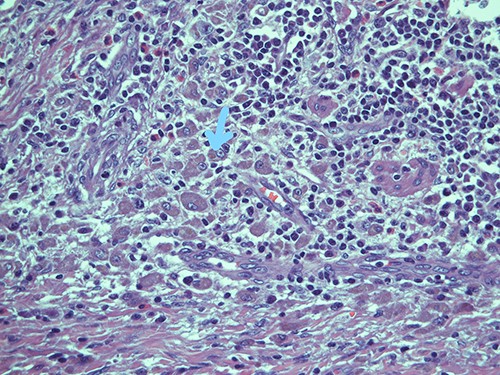

Submucosal cellular population is constituted by round histiocytic elements with a granular dense cytoplasm, containing typical eosinophilic bodies (arrow); haematoxylin and eosin, magnification ×20.

Intracellular and extracellular Michaelis–Gutmann bodies surrounded by inflammatory cell infiltrate of histiocytes; haematoxylin and eosin, magnification ×40.